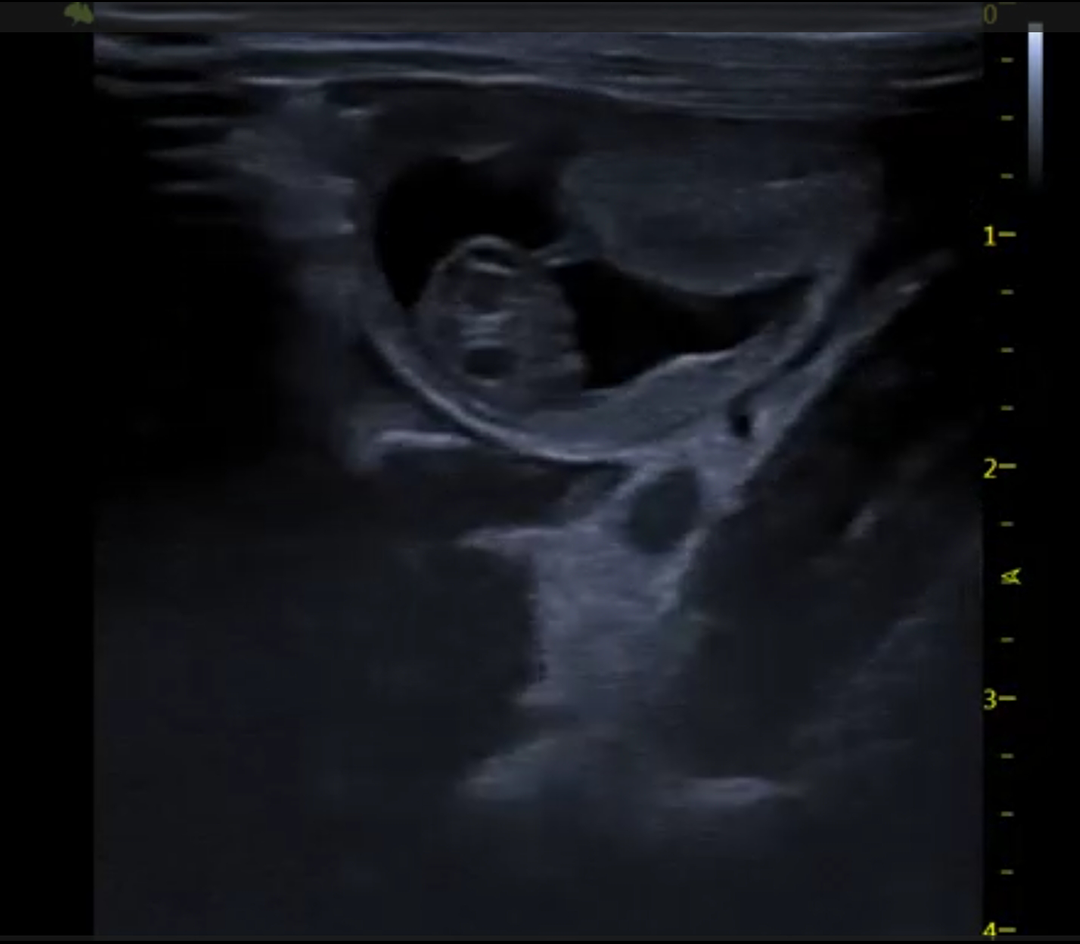

Le V6 LAB est un système d’échographie préclinique ultra-haute fréquence dédié à l’imagerie fonctionnelle et structurelle du petit animal.

Imagerie cardiaque haute cadence chez la souris et le rat

Reproduction & développement

Imagerie B-mode haute résolution

M-mode précis pour l’analyse fonctionnelle cardiaque